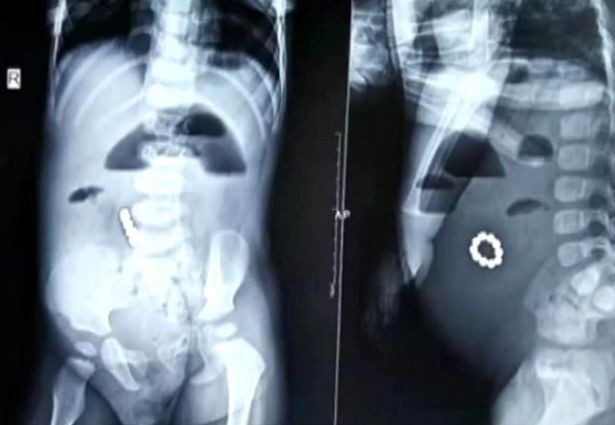

Bé trai 1 tuổi ở Trung quốc đã phải nhập viện trong tình trạng nguy kịch sau khi nuốt 10 viên nam châm vào bụng.

Theo bác sĩ nhi khoa Zhang Zhengmao, người trực tiếp khám cho cậu bé, tất cả các viên nam châm này đều hút nhau thành 1 vòng tròn khi ở trong bụng.

10 viên nam châm hút lại thành vòng tròn và hình ảnh X-quang chụp vị trí nam châm trong bụng.

Vì tai nạn này, ruột cậu bé đã bị thủng lỗ, trong lúc phẫu thuật bác sĩ còn phát hiện ra 4 chỗ bị tổn thương khác. May mắn thay ca phẫu thuật đã diễn ra tốt đẹp, các bác sĩ đã loại bỏ thành công tất cả những viên nam châm này ra khỏi người cậu bé.

Chia sẻ về tai nạn này, bác sĩ sĩ Zhengmao cho biết: "Loại nam châm nhỏ này khá nguy hiểm với trẻ nhỏ vì nó có sức từ tính mạnh. Nếu trẻ chỉ nuốt phải 1 viên thì có thể bài tiết nó ra một cách dễ dàng, nhưng thường thì trẻ hay nuốt vào bụng những vài viên liền, gây hỏng dạ dày và ruột".